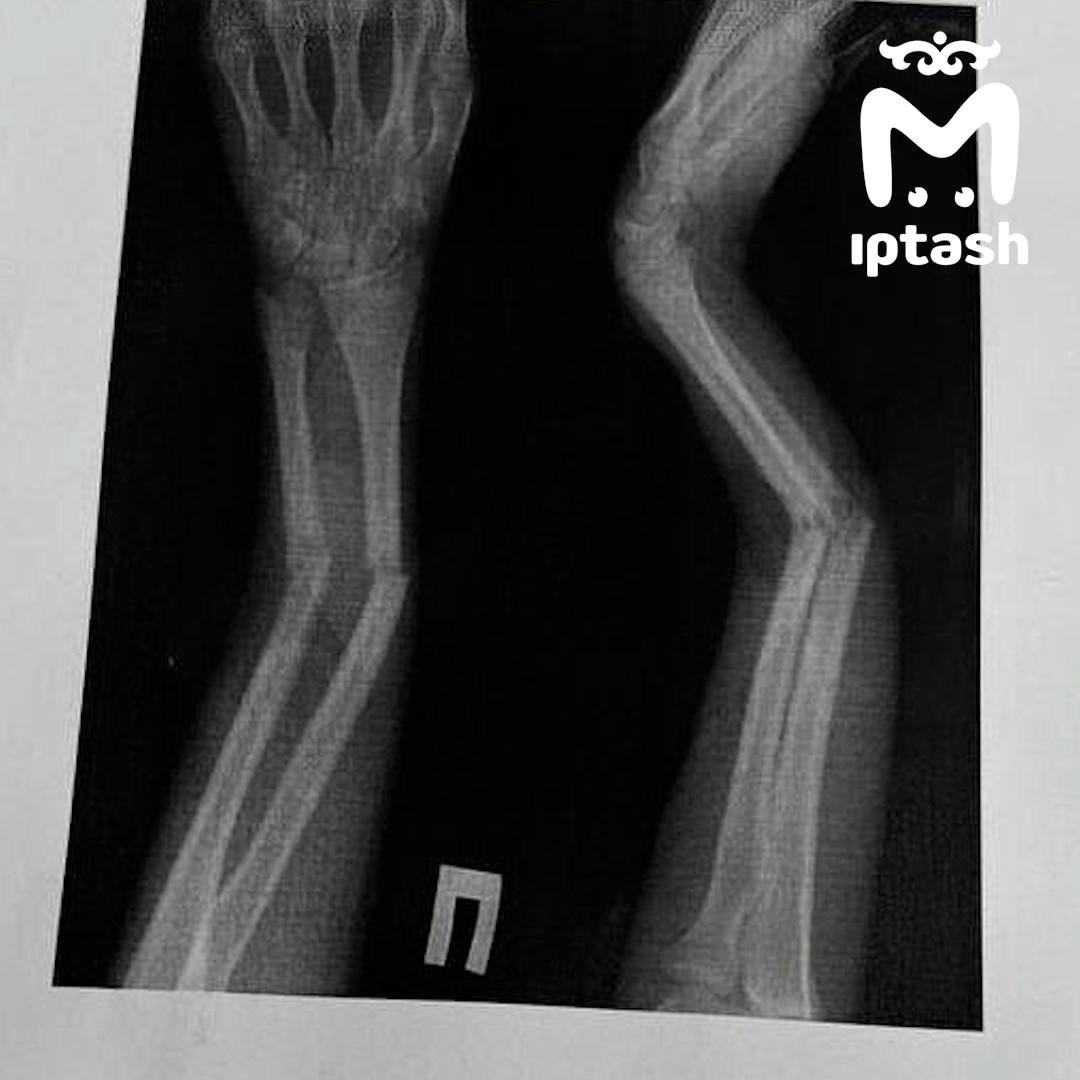

Сломали руку милому мальчику

Сломали руку милому мальчику 111 фото